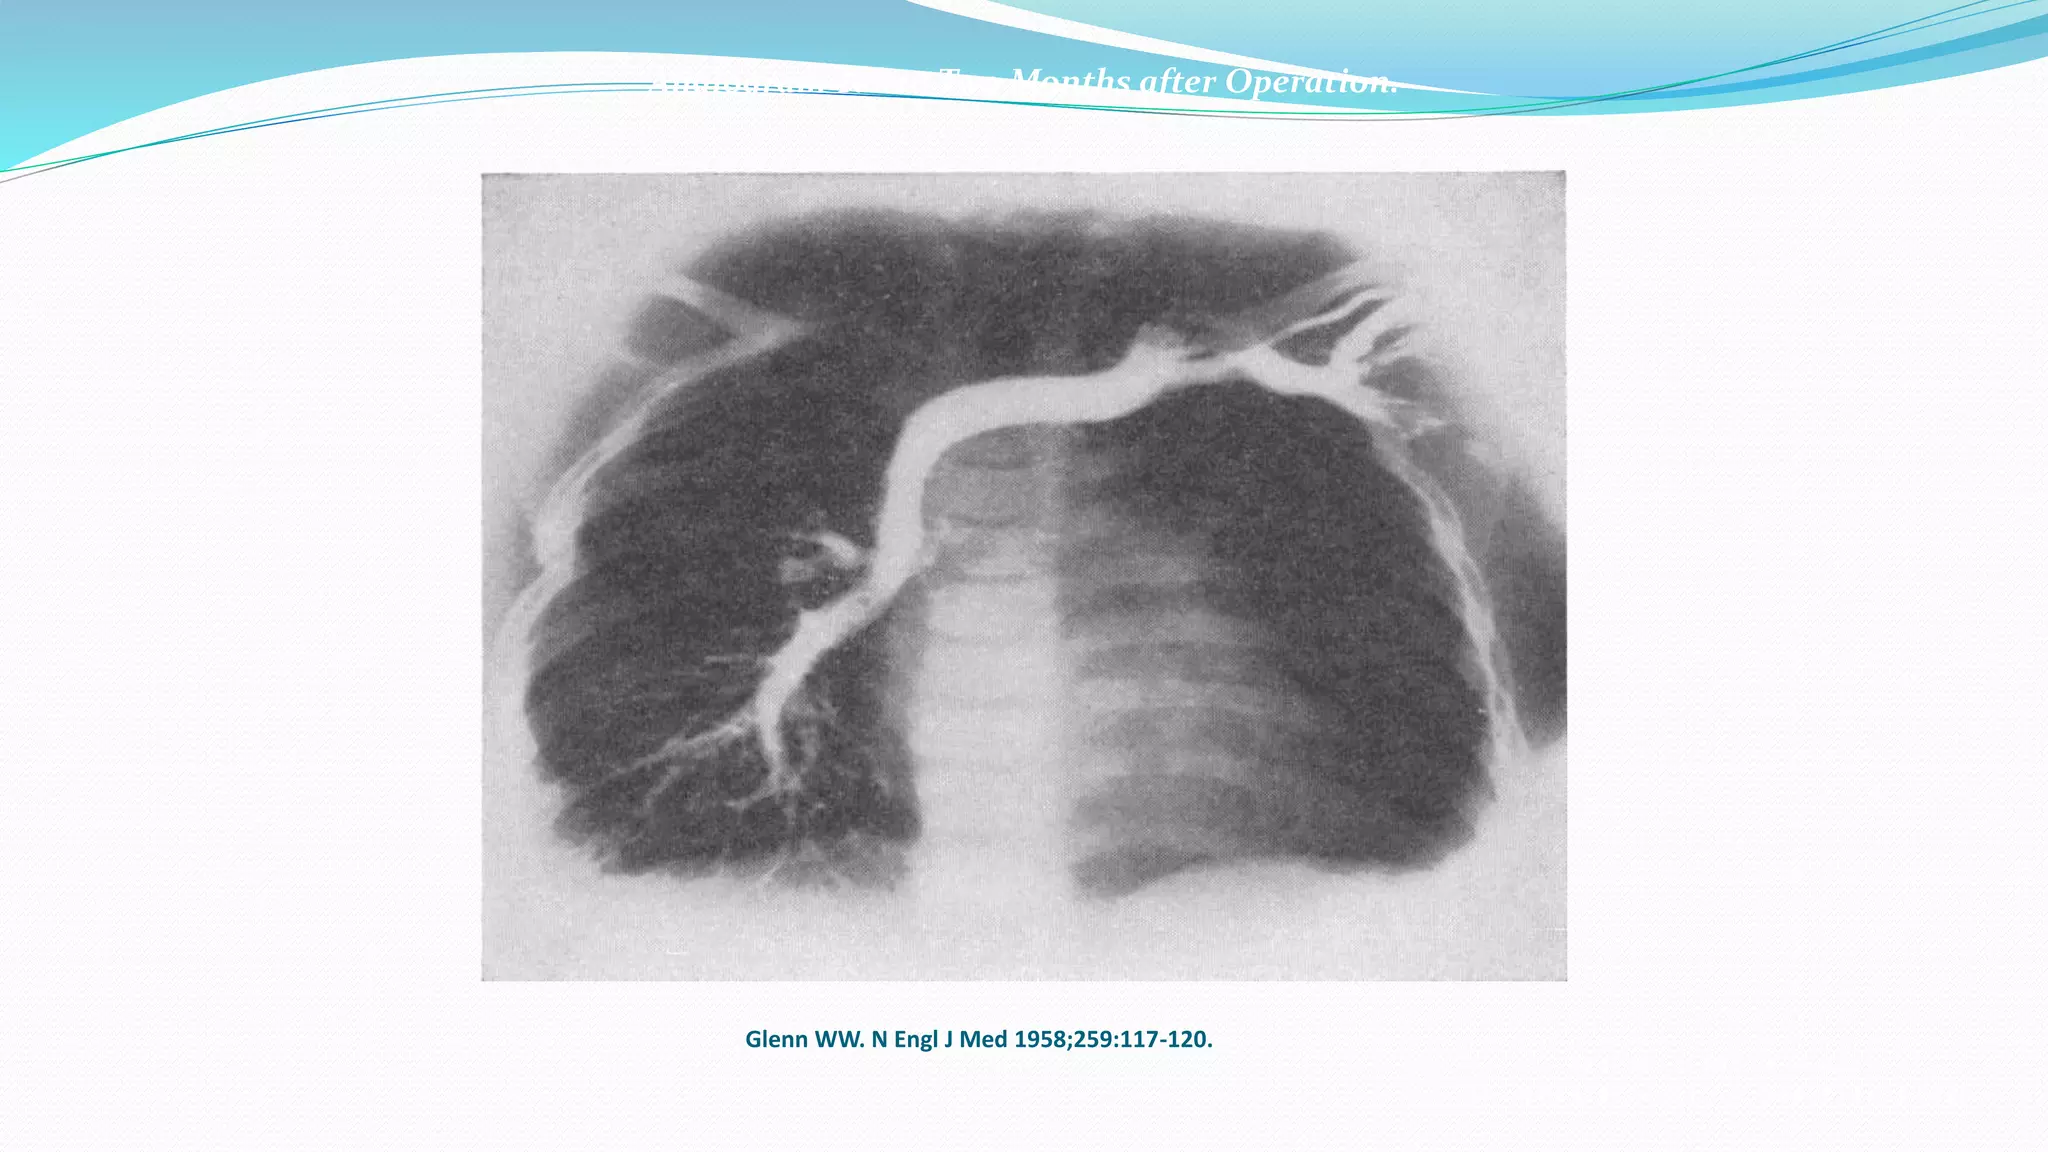

Angiogram Taken Two Months after Operation.

Glenn WW. N Engl J Med 1958;259:117-120.